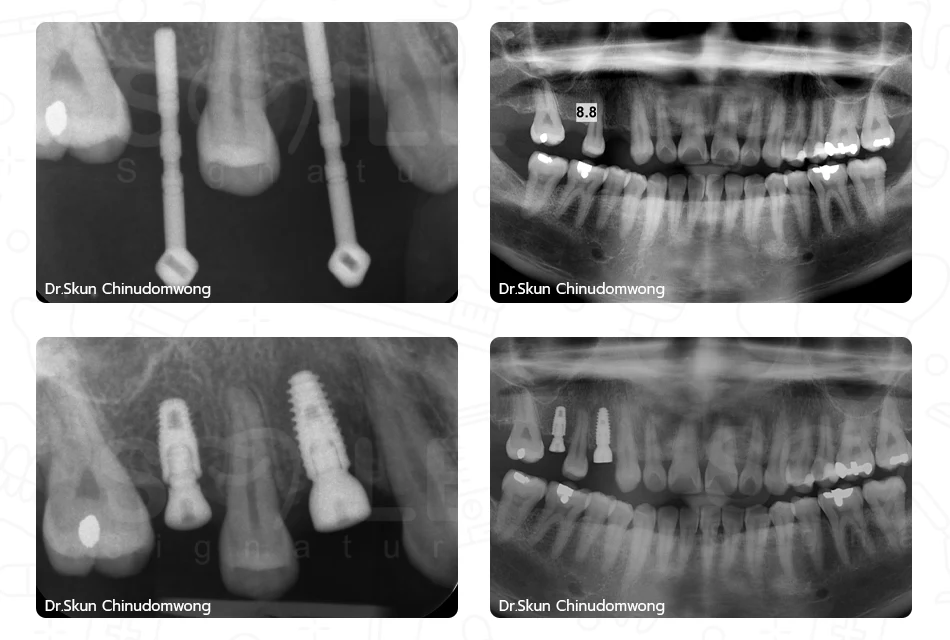

Sinus Augmentation